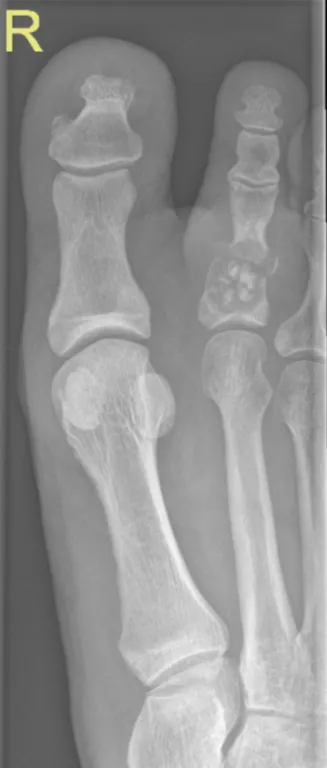

Toe Radiology Images

This collection contains 1 radiology images related to toe, including various imaging modalities such as X-rays, MRIs, CT scans, and ultrasound images commonly used in medical diagnosis and education.